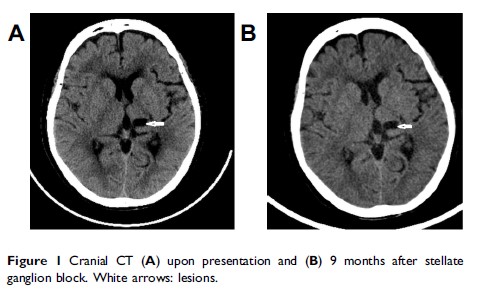

超声引导下星状神经节阻滞治疗中风后疼痛:病例报告和回顾